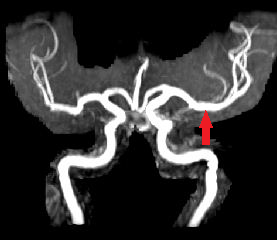

L'acquisition des images a été réalisée lors du séjour du patient en ré-éducation, 6 mois après l'apparition des symptômes. Les séquences permettent de mettre en évidence un AIC carotidien droit au stade chronique (hyposignal en pondération T1 et hypersignal en pondération T2) avec atrophie du tissu cérébral de l'hémisphère droit. L'angiographie-IRM (ARM) des vaisseaux du cou montre une dissection de l’artère carotide interne droite (aspect en flamme de bougie) avec retentissement hémodynamique d’aval.

ARM, reconstruction 3D vue de face. La flèche indique la dissection de l'artère carotide interne droite. |

- IRMsujet12211anatpathologieAVC_ARM.img : ARM des vaisseaux du cou du sujet 12211. Cette image est une reconstruction 3D. Elle apparait dans le logiciel EduAnatomist uniquement dans la fenêtre correspondant au plan axial. Le curseur situé à droite de l'image permet de la faire pivoter. Caractéristiques techniques : FOV : 512 ; résolution spatiale : 0,51 X 0,51 X 0,8mm3 ; TR : 4,32ms ; TE : 1,556ms ; Flip angle : 25°